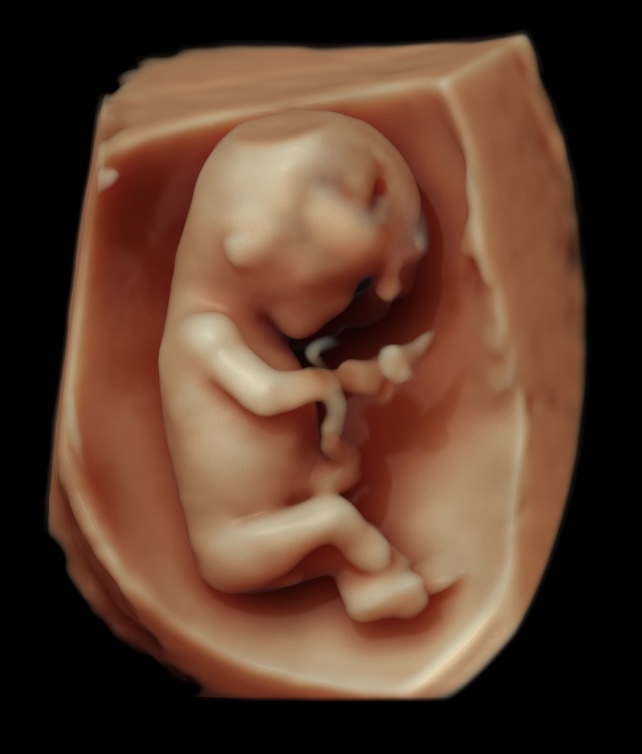

Somos expertos en detección temprana de anomalías. Brindamos una gama completa de Ultrasonidos Fetales y Ecografías 5D-7D: